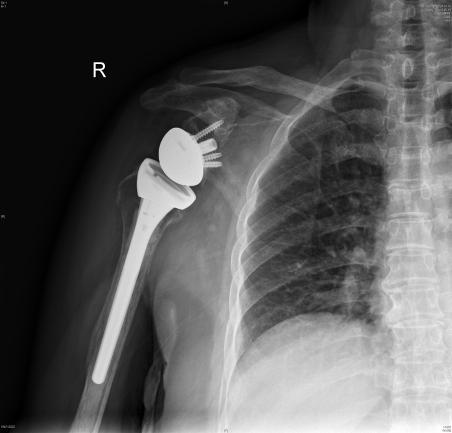

汤发强主任医师为叶女士进行全面的身体检查,经过团队讨论及专业的分析,诊断为“肱骨头坏死伴右肩骨性关节炎”,决定为她进行反向肩关节置换手术

在制定了详细的手术方案后,汤发强主任医师团队顺利完成手术。术后,团队医护人员对叶女士进行了悉心的护理和康复指导,根据她的身体状况及时调整康复计划,现已康复出院。目前叶女士的肩关节功能恢复得非常好,她又重新找回了自信和生活的乐趣。

▲术前(左)术后(右)对比

反向肩关节置换是一种较为先进的肩关节手术方式,传统肩关节置换是将肱骨头置换为假体,而反向肩关节置换则是将肩关节的球窝结构进行反转,把球形的假体安装在肩胛骨上,而把凹面的假体安装在肱骨上。

这种独特的设计改变了肩关节的生物力学机制,使得肩关节在活动时的受力点发生了转移。通过这种方式,可以更好地恢复肩关节的功能,提高患者的生活质量。